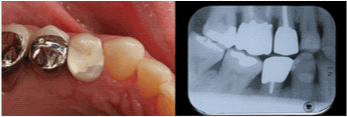

| Maxillary Right First

Premolar |

9 |

77.8% |